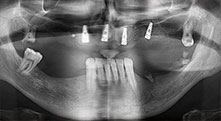

dentatura residua

Un paziente di 40 anni con una dentatura residua limitata desiderava un restauro basato su impianto. Dal momento che è un fumatore, era controindicato un rialzo del seno mascellare con una protesi fissa. È stata quindi programmata una protesi a barre.

impianti

I quattro impianti sono fissati come programmato. I molari mascellari distali possono comunque essere utilizzati per fissare la protesi in linea introdotta un mese dopo l'impianto.